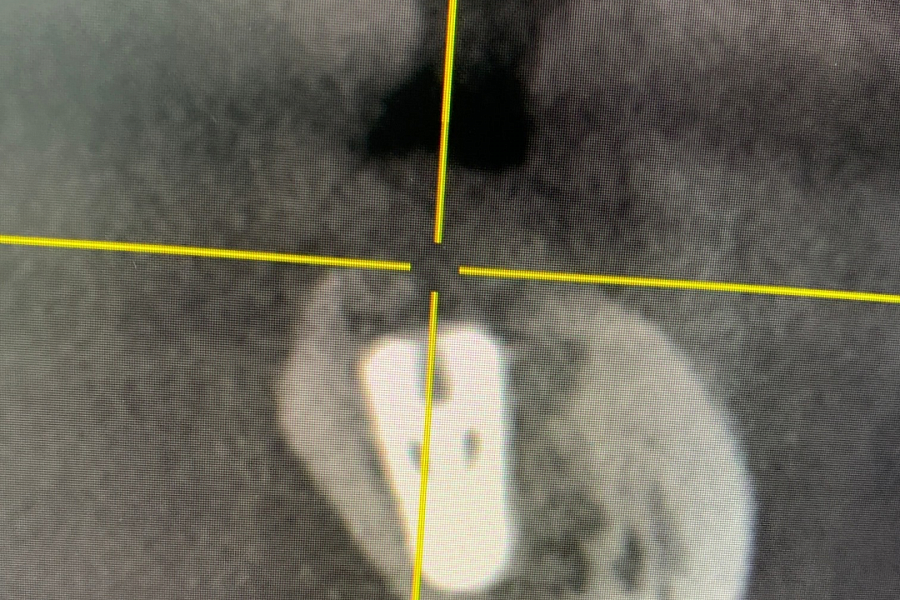

На рентгеновском снимке видим разрежение костной ткани, обширный воспалительный процесс, который находится в контакте с нижним челюстным каналом. В канале проходит нерв, вена и артерия.